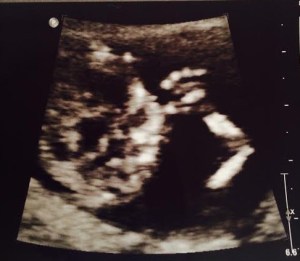

how far along: 23 weeks, 6 days {oops, a little delayed}

size of baby: a grapefruit {105-11.8 inches, 12.7-20.8 oz} not quite sure if I get this comparison…that is a VERY large grapefruit!

gender: a baby girl!